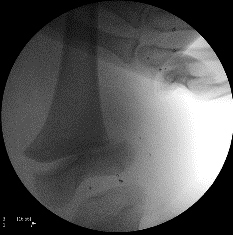

Posterior dislocations account for 80% of hip traumas. Low energy injuries cause traumatic hip dislocations in the younger child (2–5 years) due to associated ligamentous laxity. In older children (11–15years), dislocated hips are caused by higher energy injuries and have a higher association with acetabular fractures, although this is rare. Dislocations are more common than fractures in the paediatric population.

Clinically

- Posterior dislocation:Typically flexed, adducted, internally rotated hip.

- Anterior dislocation:Typically extended, abducted, externally rotated hip.

Conduct a careful neurovascular evaluation with particular attention to the sciatic nerve. Ipsilateral femoral shaft fracture should be excluded before manipulation.

Investigations

If an acetabular fracture is identified on the pre- or post-reduction X-rays, Judet (45° obturator and iliac oblique) views should be obtained. If an intra-articular fragment or incongruent reduction is present, a CT scan is indicated.

Dislocated hip. Available from:

https://commons.wikimedia.org/wiki/File:Dislocated_hip.jpg